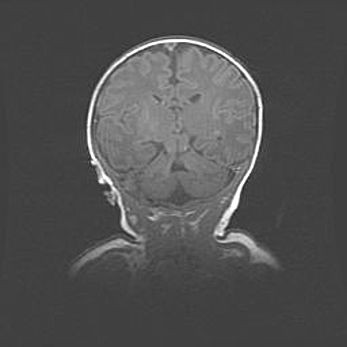

Неполная лизэнцефалия (пахигирия). Открытая гидроцефалия.

Возраст: 17 дней

Вес: 3110 г

Пол: мужской

Окружность головы: 33,5 см

Срок гестации: 35-36 недель

Лизэнцефалия—недоразвитие корковой пластинки и мозговых извилин в результате нарушения миграции нейронов коры. Поверхность мозговых полушарий гладкая. Микроскопически выявляется отсутствие нормальных слоев коры и скопление групп нейронов в подкорковом белом веществе.

Пахигирия—уменьшение числа вторичных извилин. В пораженном полушарии нервные клетки образуют толстый недифференцированный слой с неправильно расположенными нервными волокнами и группами гетеротопных клеток. Нервные клетки незрелые. Белое вещество истончено. При этом нередко аномально развит корково-спинномозговой путь.